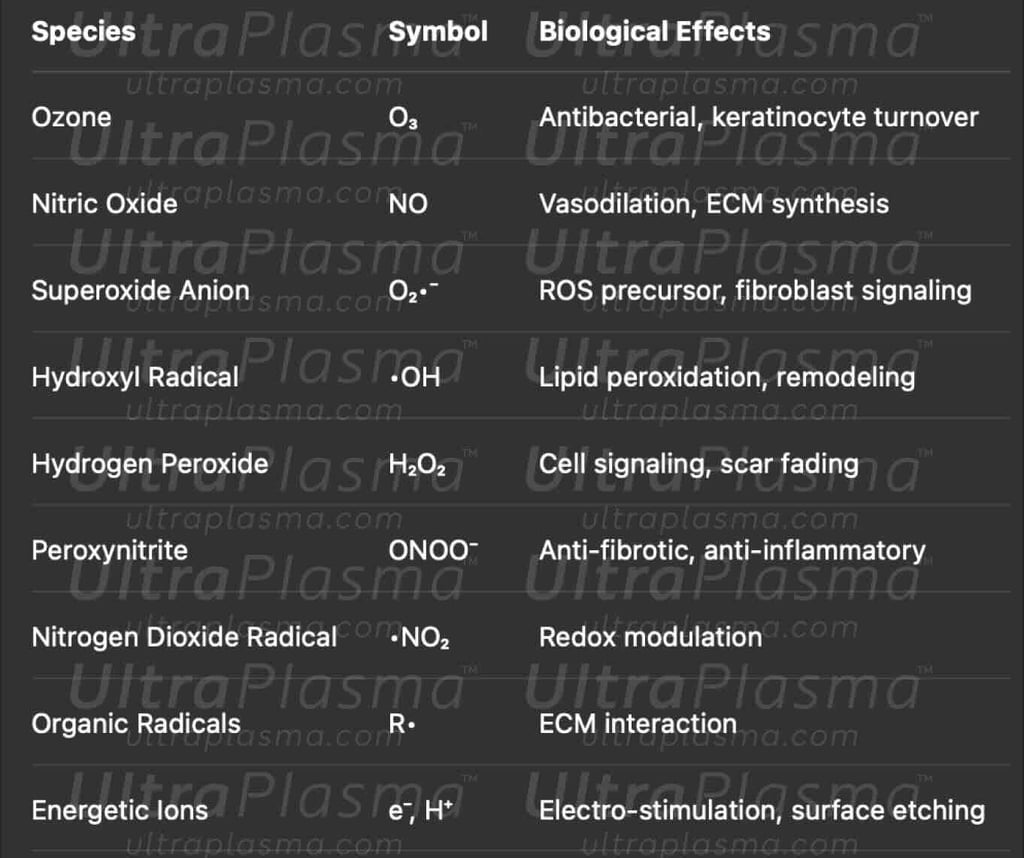

4.1 Generated Reactive Species

5. UltraPlasma™ Treatment Strategy by Scar Type